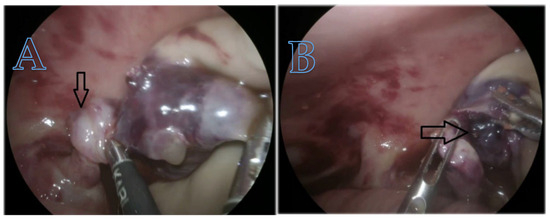

Ovarian torsion occurred in a single neonate with a complex ovarian cyst. The mixed echogenic appearance raised suspicion of torsion. This ovarian cyst occurred in a neonate with a complex ovarian cyst characterized by torsion of the infundibulum–pelvic pedicle. We performed an immediate laparoscopic procedure and subsequent removal of the right ovary. Figure 8 shows the twisted cyst as observed during the emergency procedure.

Figure 8.

(A) The arrow indicates torsion of the ovarian pedicle; (B) the arrow indicates hemorrhage and necrosis complications.